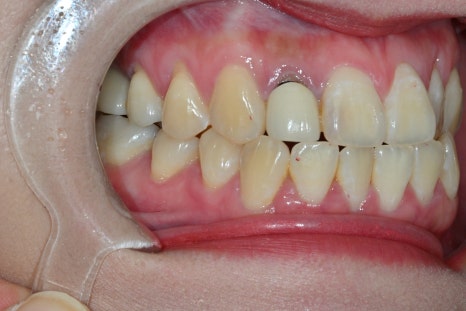

Changes after treatment

<BEFORE>

<AFTER>

Natural appearance of the gum line restored

A color harmony with the surrounding teeth

Improvement of the sense of incongruity in the front teeth

The response that it “looks like a natural tooth”

was especially impressive.